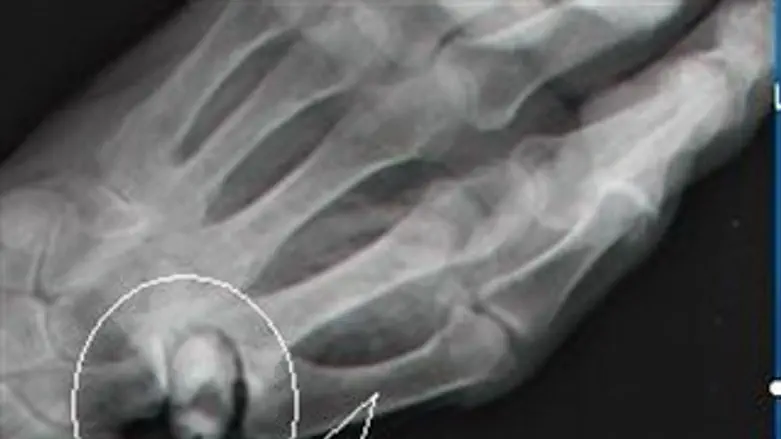

השבוע נערך, לראשונה בישראל ובעולם, ניתוח מורכב במסגרת המחלקה לכירורגיה של היד, בניהולו של ד"ר אברהם הס, להחדרת משתל בבסיס האגודל שמתכלה מעצמו ונעלם מהגוף. הניתוח החדשני, שבוצע לזהבה אוזון, תושבת ראשל"צ, עושה שימוש במשתל (פרוטזה) חדשני המורכב מבלון המתנפח וממלא את החלל הנוצר לאחר כריתת עצם הטרפז בבסיס האגודל. לאחר מספר חודשים המשתל מתכלה ונעלם מהגוף לחלוטין ובמקביל - מתחזקת האחיזה של בסיס האגודל בכף היד.

במקרים בהם נכשל הטיפול שמרני שכולל פיזיוטרפיה, טיפול בכדורים והזרקת סטרואידים, מוצע ניתוח בהרדמה כללית של כריתת עצם הטרפזיום (עצם בצורת טרפז בבסיס האגודל) המרכיבה את בסיסו של המפרק האוכפי בבסיס האגודל. "במהלך הניתוח עושים לעיתים שימוש בשתלים קבועים כדי למלא את החלל שנוצר עם הרחקת הטרפזיום. קיימת נטייה בשתלים הקבועים להישחק או להישבר עם הזמן וכוח האחיזה לאחר הניתוח יורד בכ 30%", הוא מסביר, "ומכאן החשיבות הגדולה של המשתל הנספג והמתכלה מעצמו".

"נעשו מאמצים רבים בעולם לפתח משתל מתכלה, ולשמחתנו, לראשונה בעולם הוא יושם בבית החולים קפלן", אומר ד"ר אורון. "המשתל המתכלה ממלא את החלל שנוצר, משמר את גודלו וכך מבטיח שיקום מואץ ותוצאה כירורגית משביעת רצון". הרופאים מאמינים שהשימוש במשתל מתנפח ומתכלה יאפשר שמירה על כוח האחיזה של האגודל באופן אופטימלי. "המשתל שומר על המרווח שבו היתה מונחת העצם שנכרתה וכך נשמר המתח באורך השרירים והגידים שמאפשרים אחיזת האגודל. היתרון במשתל המתכלה הנו שהוא מאפשר בנייה של רקמת צלקת תומכת משמעותית ולאחר מספר חודשים הוא נספג ומחליפה אותו רקמה פיברוטית חדשה. כך, למעשה, נמנעים סיבוכים שאפיינו משתלים שנוסו בעבר ושאינם מתכלים".